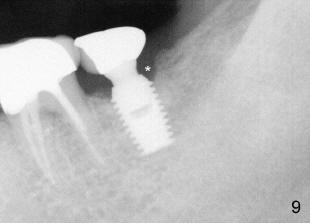

The patient has complained discomfort since cementation. Fig.9,10 X-ray was taken 11 months post-cementation, showing bone resorption, particularly in the distal aspect of the crest (*). At that time, there was food impaction between #18 and 19. Pick-up impression was taken to modify contact area of #18.